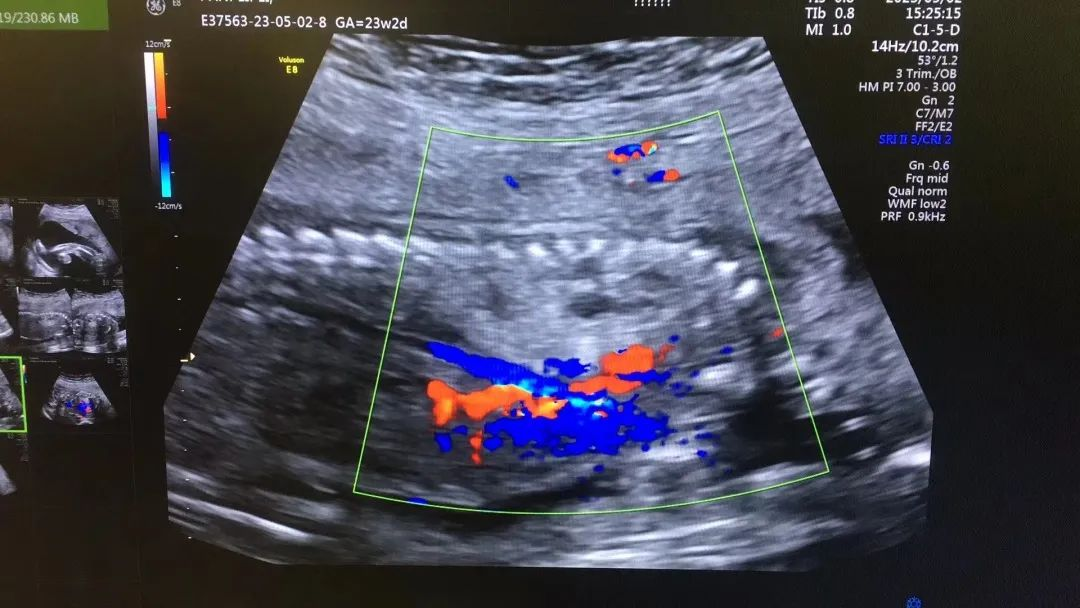

近日,我院超聲科醫(yī)生在給孕中期孕媽做四維彩超檢查時(shí),發(fā)現(xiàn)胎兒查出異常,孕媽想留下這個(gè)寶寶,陷入了兩難。

武漢的劉女士(化名),前幾個(gè)月剛懷上寶寶,全家都特別高興。懷孕23周+時(shí),劉女士在家人的陪伴下來(lái)到武漢仁愛(ài)醫(yī)院超聲科做了四維彩超檢查,當(dāng)醫(yī)生拿出檢查報(bào)告的時(shí)候,劉女士卻當(dāng)場(chǎng)傻眼了,原來(lái),在四維彩超的報(bào)告里,診斷出了胎兒右肺囊性腺瘤樣病變,她的心頓時(shí)揪了起來(lái)!

劉女士看到檢查結(jié)果后,擔(dān)心該病變會(huì)影響腹中寶寶的健康,考慮是否應(yīng)該終止妊娠。隨即,武漢仁愛(ài)醫(yī)院超聲科王娟主任為劉女士耐心地解釋:“先天性肺囊腺瘤是一種肺組織錯(cuò)構(gòu)畸形,先天性肺囊腺瘤畸形病例約70%的腫塊大小較穩(wěn)定;約20%腫塊產(chǎn)前明顯縮小或消失;僅10%腫塊是進(jìn)行性增大。單純的先天性肺囊腺瘤(CCAM)無(wú)水腫的胎兒可以密切隨訪,在28周前接受連續(xù)超聲復(fù)查,CVR<1.6,一般超聲動(dòng)態(tài)監(jiān)測(cè)2~4周監(jiān)測(cè)一次,而對(duì)于CVR≥1.6的需要在28周前每周1-2次的超聲監(jiān)測(cè),防止出現(xiàn)胎兒水腫,直到分娩。”